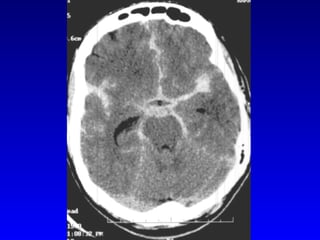

Probability of detection of SAH on CT after the initial event Day 0 95% Day 3 75% 1 week 50% 2 weeks 30% 3 weeks almost 0% Evans RW 1999

Probability of detectionof SAH on CT after the initial event Day 0 95% Day 3 75% 1 week 50% 2 weeks 30% 3 weeks almost 0% Evans RW 1999